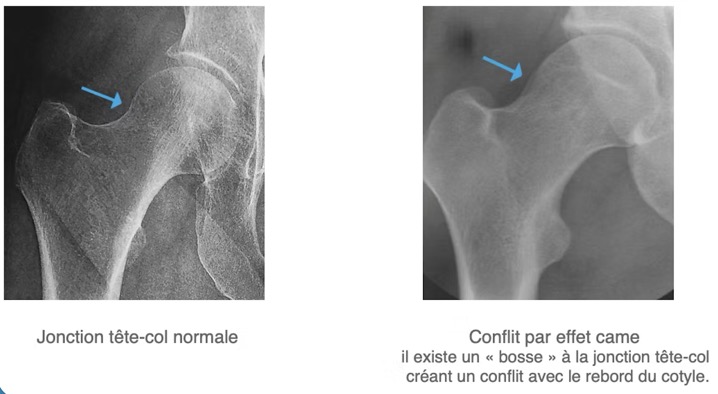

- 1. Le conflit de type CAM (a): excès d'os de la tête et le col fémoral => pas parfaitement ronds